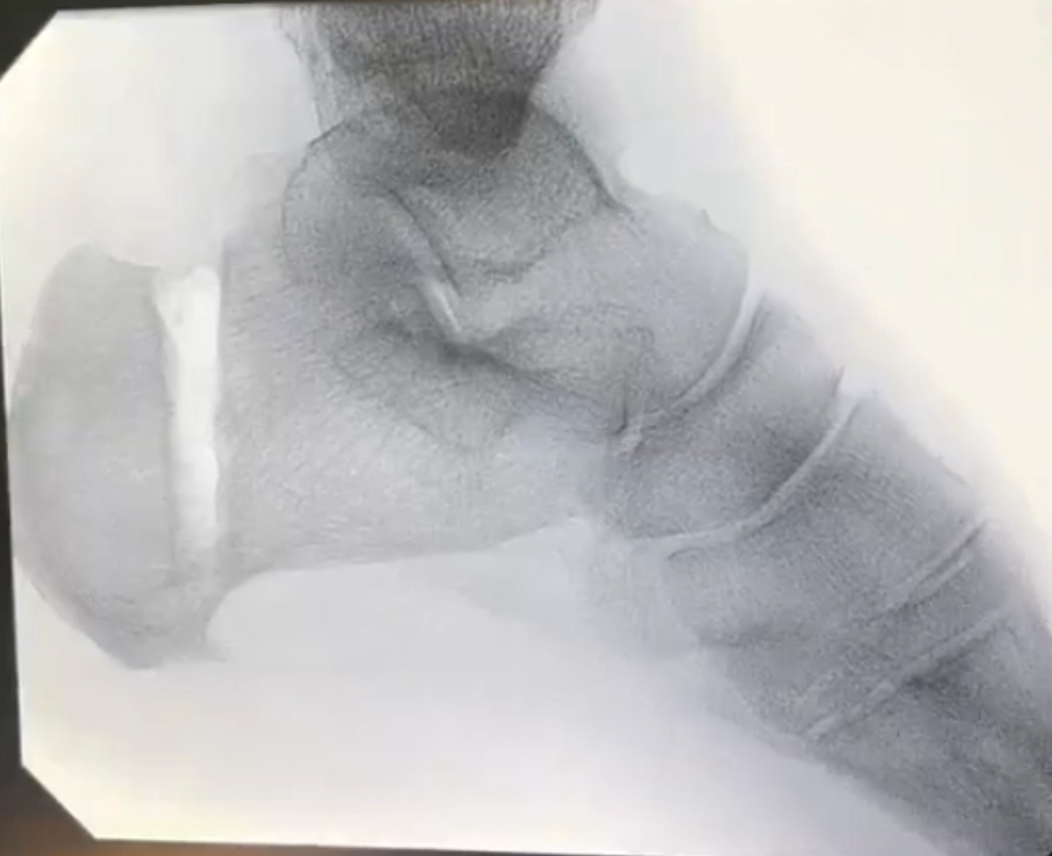

What problems is surgery addressing?

Insertional Achilles tendinopathy involves pain where the tendon attaches to the heel bone and may include:

- Degenerative tendon tissue

- Bony prominence or heel spur

- Compression of the tendon against the heel bone

Common surgical procedures

- Removal of damaged tendon tissue

- Excision of bony prominence or heel spur

- Partial detachment and re-attachment of the Achilles tendon, when necessary, using strong anchors

- Gastrocnemius lengthening to reduce tendon strain and improve outcomes

- Zadeks procedure - taking a wedge out of the heel bone to take the prominence away from the Achilles tendon